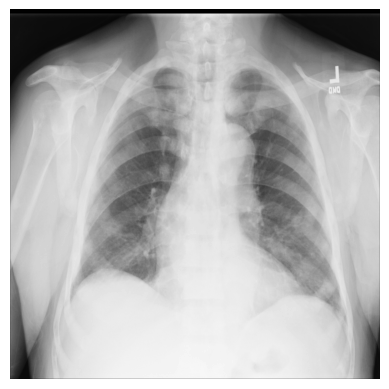

让我们从 ChestX-ray8 数据集中的一个 X 射线图像开始,进行一个简单的示例。

文件 00000011_001.png 已经为您下载并保存在 /tutorial-x-ray-image-processing 文件夹中。

1. 使用 imageio 加载图像:

import os

import imageio

DIR = "tutorial-x-ray-image-processing"

xray_image = imageio.v3.imread(os.path.join(DIR, "00000011_001.png"))

2. 检查图像的形状是否为 1024x1024 像素,并且数组由 8 位整数组成:

print(xray_image.shape)

print(xray_image.dtype)

(1024, 1024)

uint8

3. 导入 matplotlib 并以灰度色图显示图像:

import matplotlib.pyplot as plt

plt.imshow(xray_image, cmap="gray")

plt.axis("off")

plt.show()